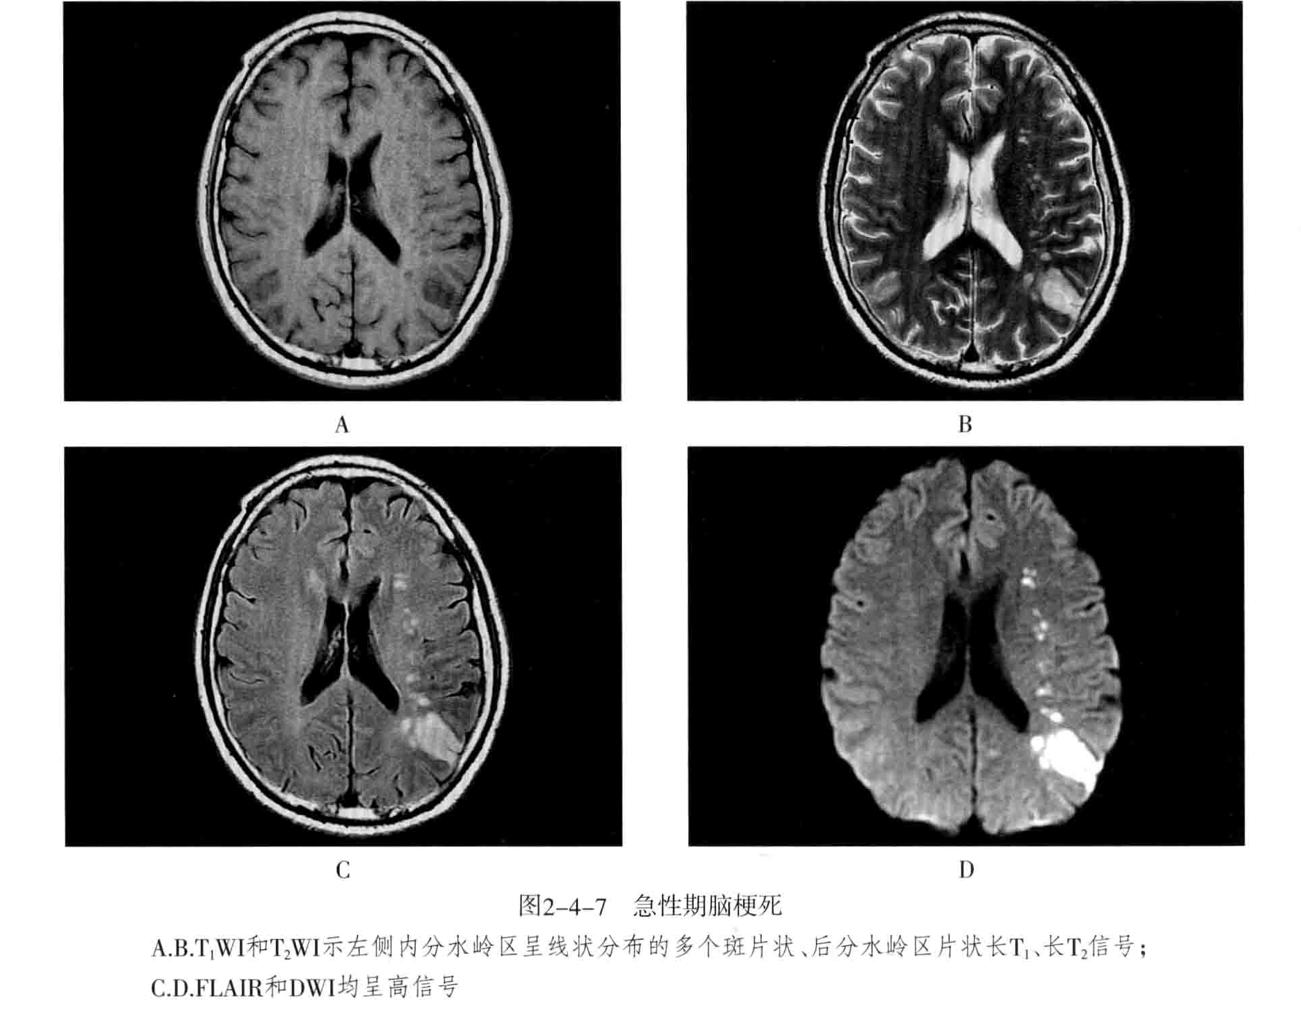

八、脑梗死:是一种缺血性脑血管疾病,常见有动脉闭塞性梗死和腔隙性脑梗死。主要病因为脑的大或中等管径的动脉发生粥样硬化,继发血栓形成,导致管腔狭窄、闭塞。以大脑中动脉闭塞最常见。脑梗死发生4-6小时脑组织发生缺血与水肿,继而脑组织出现坏死。1-2周后脑组织水肿逐渐减轻,坏死脑组织液化,梗死区出现吞噬细胞浸润,清除坏死组织,同时有胶质细胞增生和肉芽组织形成,8-10周后形成含液体的囊腔即软化灶。少数缺血性脑梗死在发病24-48小时后可因再灌注而发生梗死区内出血,转为出血性脑梗死。常见症状为偏瘫和偏侧感觉障碍、偏盲、失语等。

- CT表现为脑组织内低密度灶,梗死后2-15天为脑水肿高峰期,此时可有脑水肿表现;梗死1个月以后,相邻部位的脑室、脑池或脑沟扩大,出现脑萎缩表现。增强后梗死区可出现不均匀强化,呈脑回状、条状、环状或结节状强化。梗死区强化是由于血脑屏障破坏、新生毛细血管和血液灌注过度所致。

- MRI在脑梗死6小时之内,由于细胞毒性水肿,DWI可发现高信号,此后发生血管源性水肿、细胞死亡、髓鞘脱失、血脑屏障破坏,T1与T2弛豫时间延长。梗死后期,小的病灶不显示,表现为脑萎缩,大的病灶表现为软化灶。